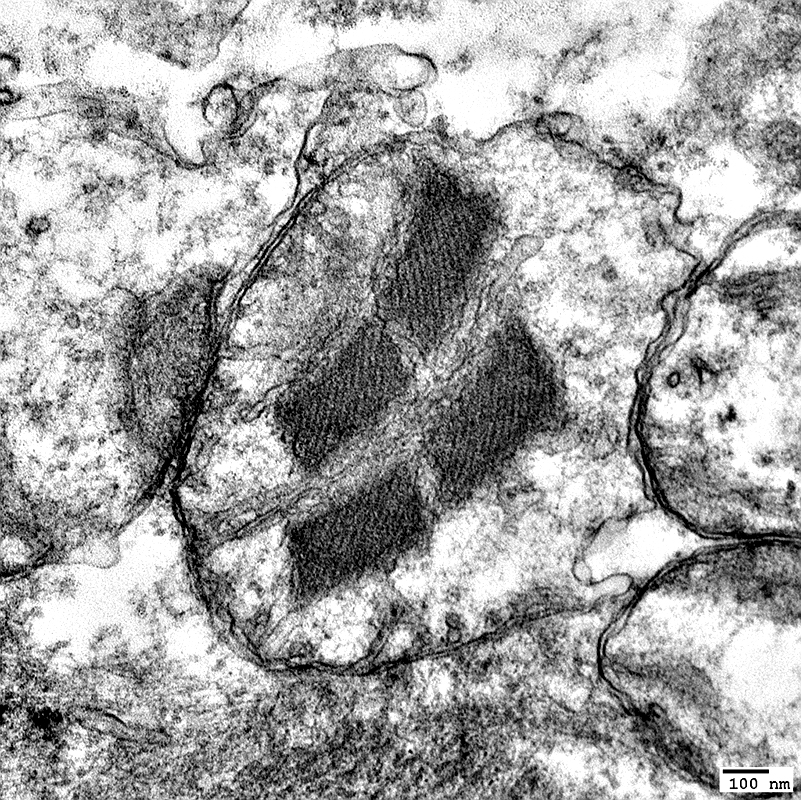

MNGIE: Muscle Ultrastructure

From: R Schmidt